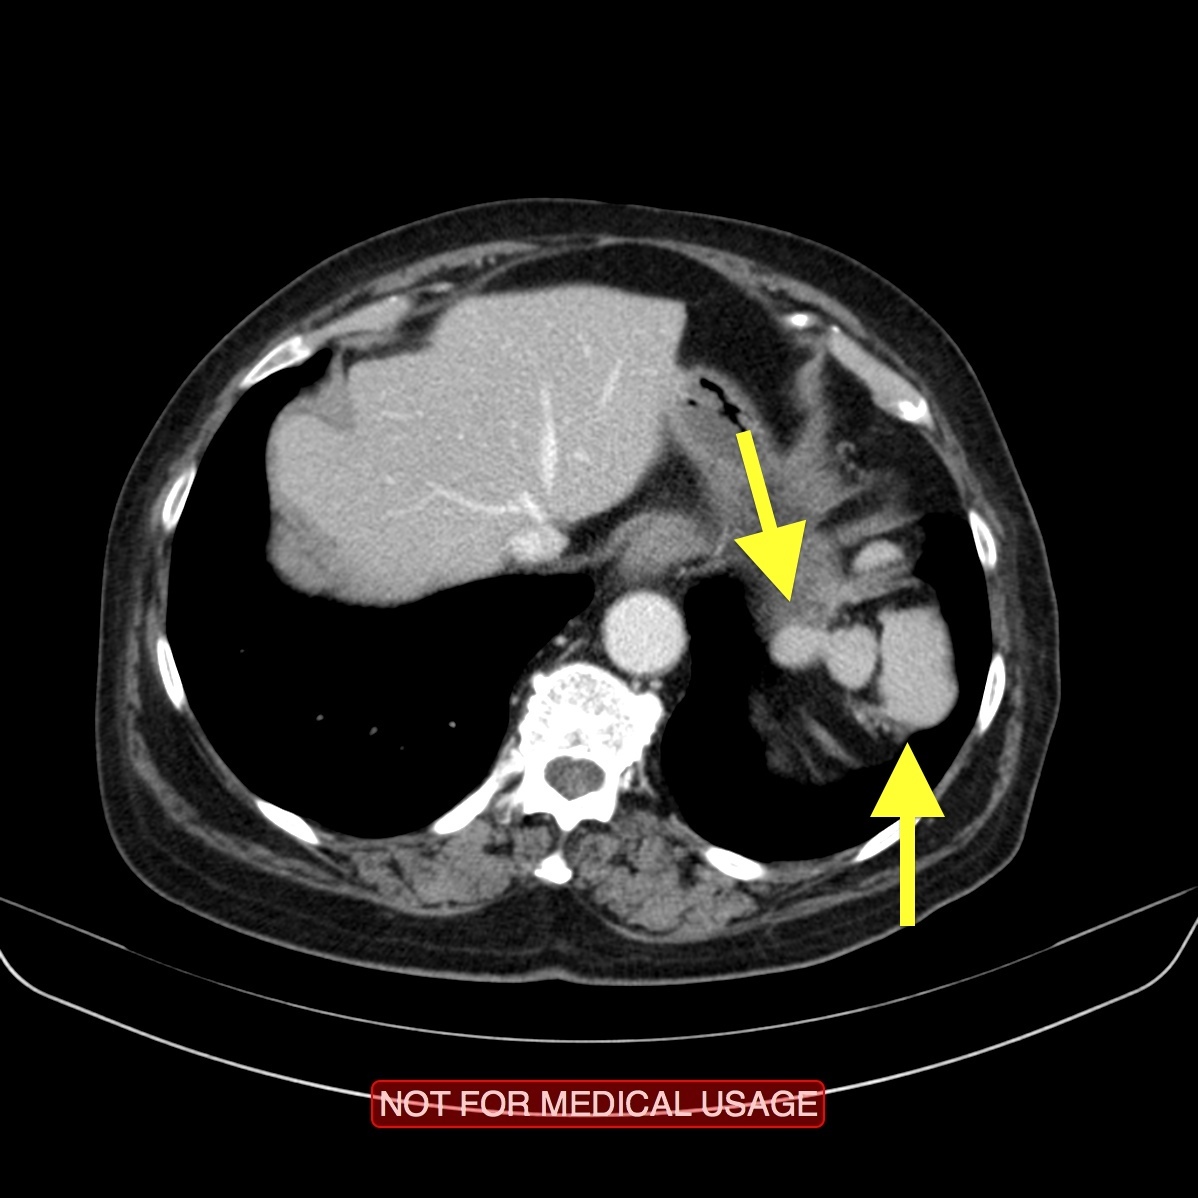

The pancreas appears bulky and shows an ill-defined isodense hypoenhancing mass measuring approximately 4.3 x 2.0 cm. There is extensive polypoidal thickening of upper gastrointestinal tract wall, involving the pylorus of stomach, duodenum, jejunum and proximal ileum. The polyps measure 5 to 30 mm and causing luminal compromise. The proximal small bowel appears distended till distal ileum and there is an ileo-ileal intussusception noted in the distal ileum. The terminal ileum and large bowel appear collapsed.

There are few enlarged non-necrotic lymph nodes noted in the mesentery, the largest lymph node measures 1.3 x 0.8 cm in size. There is a well defined oval mass measuring approximately 6.0 x 4.5 cm noted in the right adnexa. The right ovary could not be separately visualized from the mass. The mass shows post contrast enhancement and central non-enhancing necrotic region within.

Extensive polypoidal mucosal thickening predominantly affecting the upper gastrointestinal tract with pancreatic and ovarian neoplasms are likely to represent gastrointestinal polyposis syndrome most likely Peutz Jeghers Syndrome.